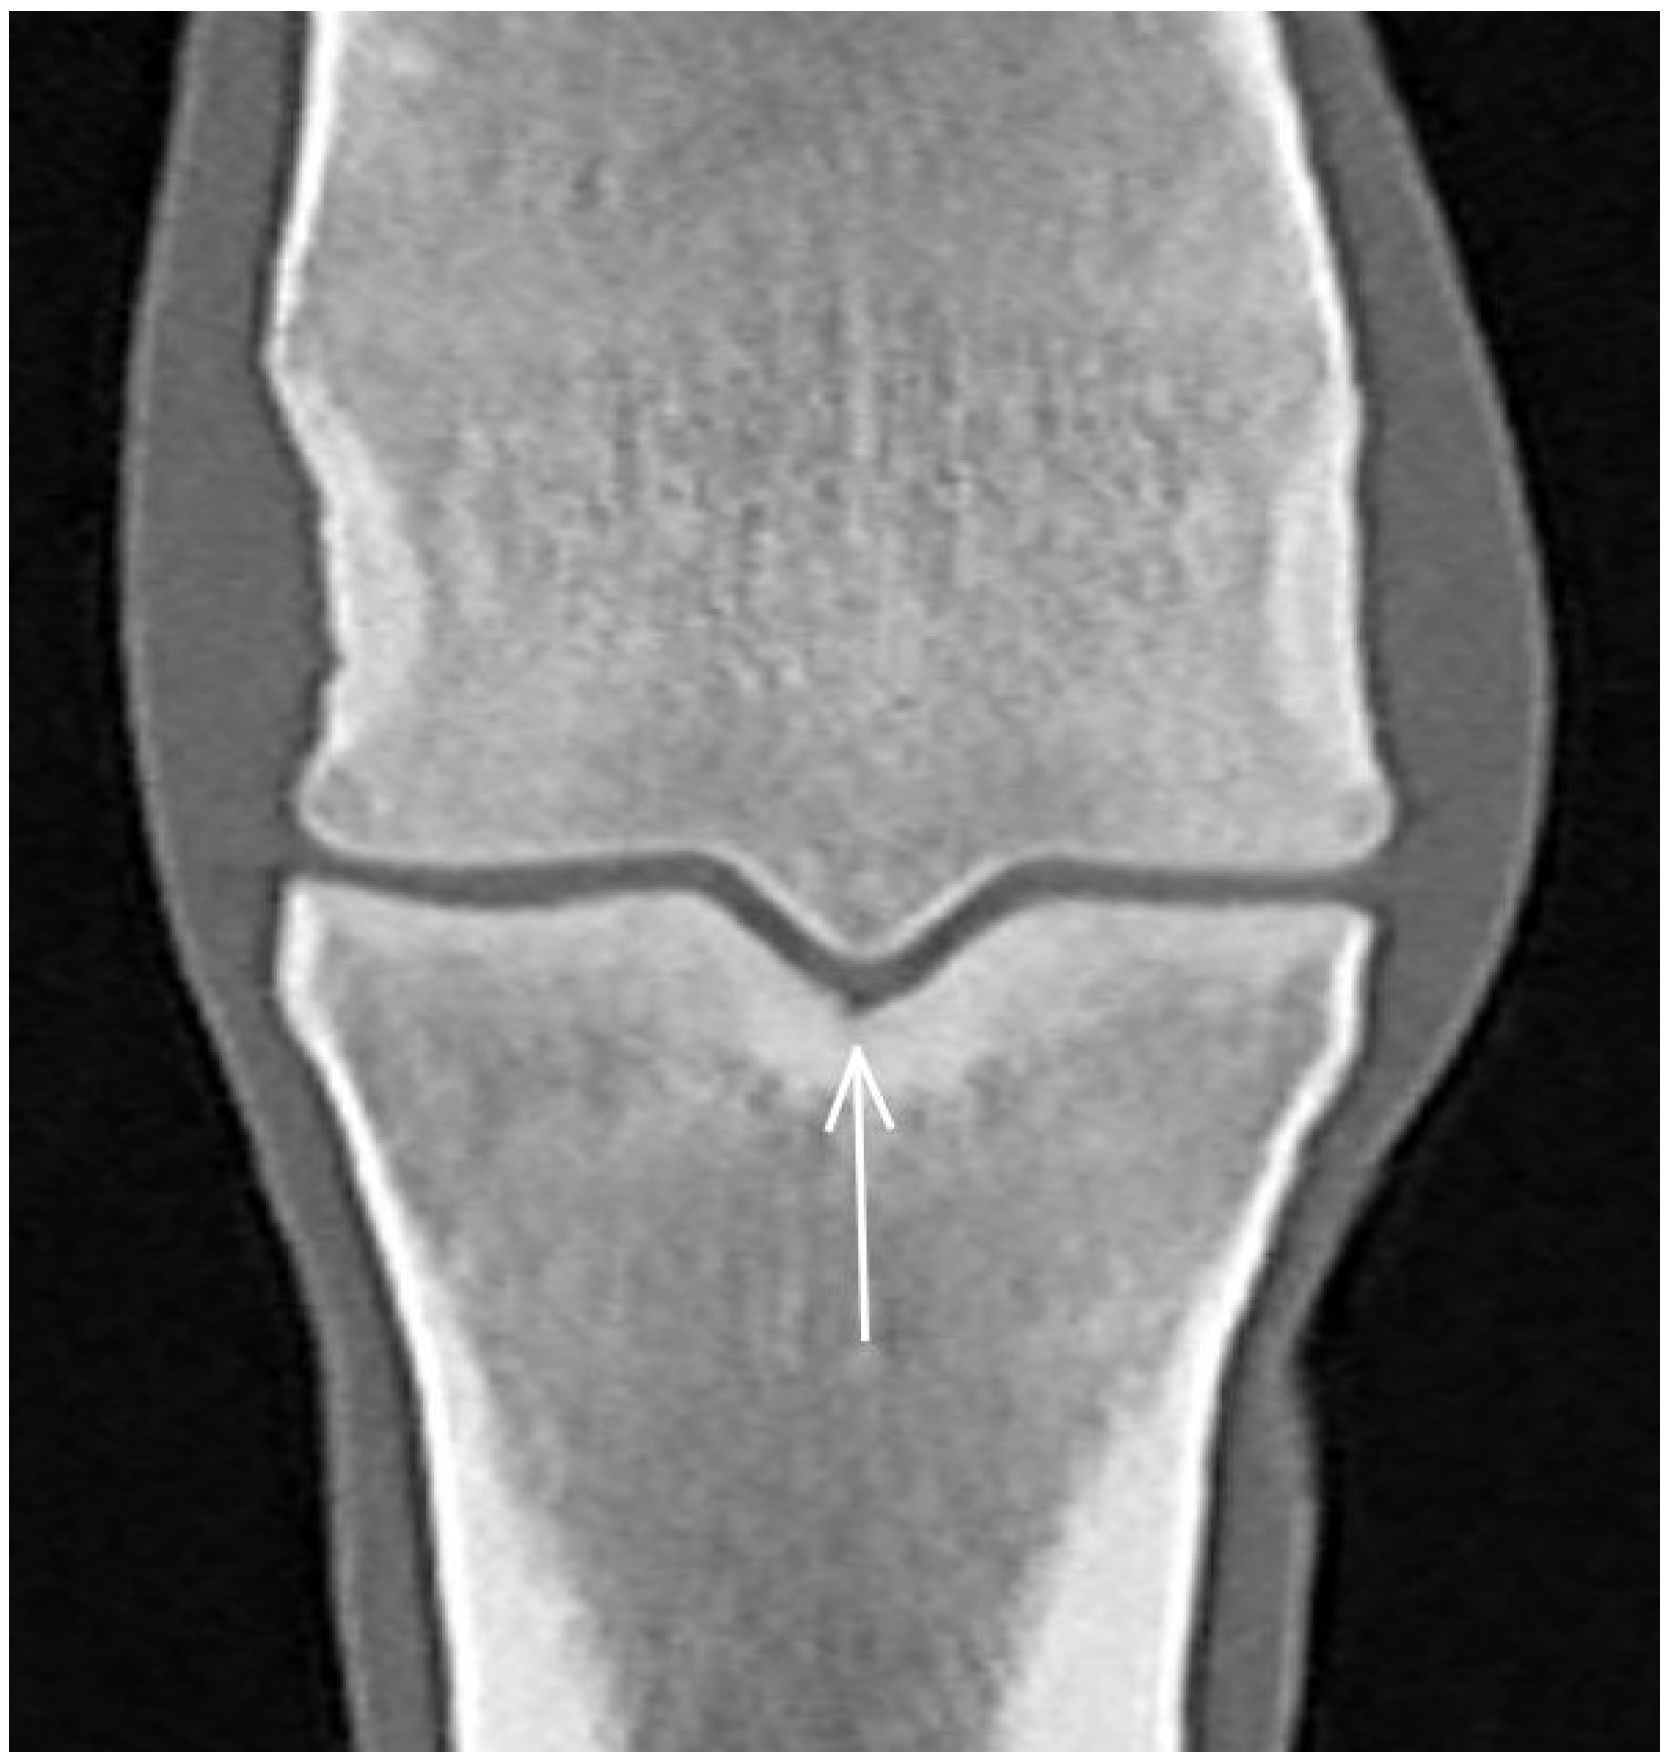

| Hypoattenuating lesion in the dorsal subchondral bone Subchondral bone thickening Dorsal/palmar half Increased attenuation in the trabecular bone Dorsal/palmar half Cone shaped/patchy Focal separated hyperattenuation | Hyperintense signal in the dorsal subchondral bone Subchondral bone thickening Dorsal/palmar half Decreased signal intensity in the trabecular bone Dorsal/palmar half Cone shaped/patchy Focal separated intermediate/low signal intensity | Radiolucent lesion Subchondral bone thickening Dorsal Increased trabecular bone opacity | |

| Medial/lateral condyle | |||

| Subchondral bone thickening Dorsal/palmar half Increased attenuation in the trabecular bone Dorsal/palmar half Hypoattenuating lesion in the subchondral bone Location | Subchondral bone thickening Dorsal/palmar half Decreased signal intensity in the trabecular bone Dorsal/palmar half Increased signal intensity in the subchondral bone Location | Increased opacity in the trabecular bone Lucent lesion in the subchondral bone Location | |

| Proximal phalanx Sagittal groove | |||

| Subchondral bone thickening Dorsal/middle/palmar third Increased attenuation in the trabecular bone Hypoattenuating lesion in the subchondral bone Location | Subchondral bone thickening Dorsal/middle/palmar third Decreased signal intensity in the trabecular bone Increased signal intensity in the subchondral bone Location | Subchondral bone thickening Increased opacity in the trabecular bone Lucent lesion in the subchondral bone Location | |